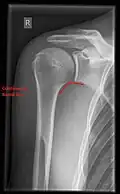

- Y-projection

The lateral contour of the shoulder should be positioned in front of the film in a way that the longitudinal axis of the scapula continues parallel to the path of the rays. This method reveals:[26]

- The horizontal centralization of the humerus head and socket

- The osseous margins of the coraco-acromial arch and hence the supraspinatus outlet canal

- The shape of the acromion

This projection has a low tolerance for errors and, accordingly, needs proper execution.[26] The Y-projection can be traced back to Wijnblath’s 1933 published cavitas-en-face projection.[27]

Y-projection conventional radiography